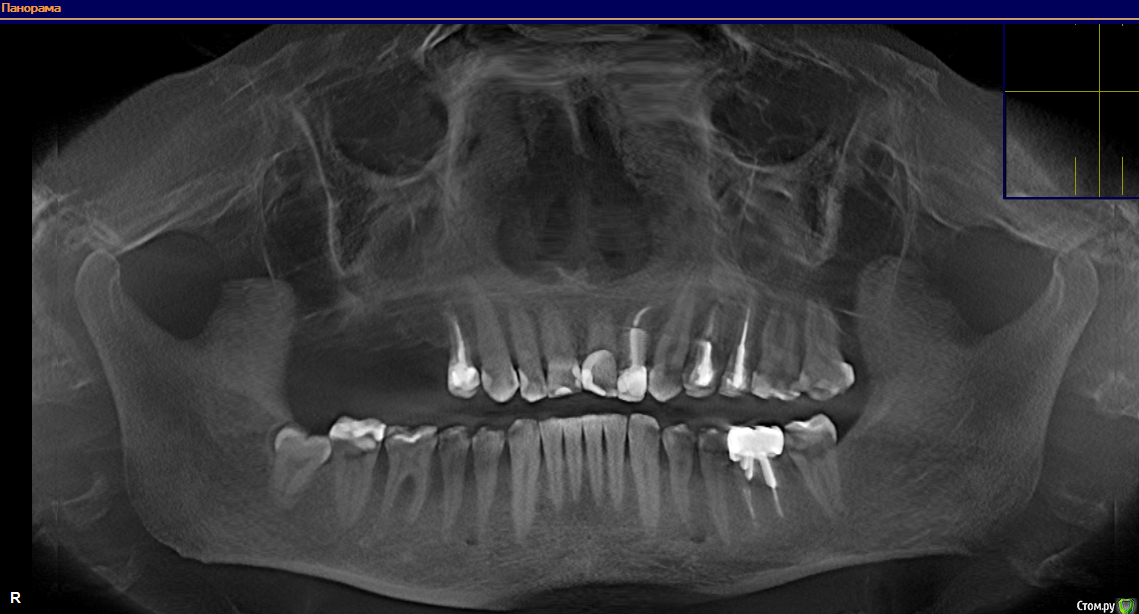

Alcort Опубликовано 6 декабря, 2018 Поделиться Опубликовано 6 декабря, 2018 (изменено) Здравствуйте. В начале этого года у меня образовался правосторонний концевой дефект на верхней челюсти. Хирург в одной стоматологии сказал что синус-лифтинг не нужен, придется делать наращивание кости, так как образовалась ямка. В другой стоматологии сказали что можно ставить имплантаты, проблем нет. В первой стоматологии Гнатолог -ортопед-хирург-имплантолог (делает все сам), в другой стоматологии вроде тоже хирург матерый. И вот я не знаю кому верить, может сходить еще в одну стоматологию? Хотелось бы услышать Ваше мнение. Здесь iso образ диска 3D томографии который можно смонтировать даймонт тулсом например, всего 300 мегабайт.https://yadi.sk/d/uE1Lyitu0a-QkA Изменено 6 декабря, 2018 пользователем Alcort Ссылка на комментарий

Alcort Опубликовано 6 декабря, 2018 Автор Поделиться Опубликовано 6 декабря, 2018 (изменено) https://yadi.sk/d/R54z8DLVWu5XJg Концевой дефект возник после удаления мостика с опорой на 6 зуб за место пятерки был искуственный зуб, семерку удалил года 4 назад, спустя год пришлось удалить и пятерку, в итоге поставил мост (Г-образный что ли) с опорой на одну шестерку, который простоял до января этого года по причине свища. С отекшей десной проходил пол года, сильную боль подавил антибиотиками по рецепту ортопеда, на протяжении 4-6 месяцев боль возникала при жевании твердой пищи, после чего обратился в государственную стоматологию и мне его удалили. Изменено 6 декабря, 2018 пользователем Alcort Ссылка на комментарий

Борис80 Опубликовано 7 декабря, 2018 Поделиться Опубликовано 7 декабря, 2018 по мне достаточно костной ткани в области и 16 и 17 отсутствующих зубов, наличие и достаточность мягких тканей можно оценить только при очном осмотре Ссылка на комментарий

Alcort Опубликовано 7 декабря, 2018 Автор Поделиться Опубликовано 7 декабря, 2018 по мне достаточно костной ткани в области и 16 и 17 отсутствующих зубов, наличие и достаточность мягких тканей можно оценить только при очном осмотреДобрый вечер. Предложили нарастить кость на месте зуба №15 так как на месте 17 не достаточно высоты из-за того что нижние зубы выдвинулись. Ссылка на комментарий

Борис80 Опубликовано 7 декабря, 2018 Поделиться Опубликовано 7 декабря, 2018 по прежнему на основании снимков не вижу ничего критичного Ссылка на комментарий

Alcort Опубликовано 7 декабря, 2018 Автор Поделиться Опубликовано 7 декабря, 2018 Спасибо за ответ, мне очень важно Ваше мнение. Скажите, что вы думаете по поводу зуба №12 могу ошибаться в нумерации, это соседний с клыком премоляр в верху с левой стороны (не там где концевой дефект) Мне предложили его удалить из-за кариеса корня, зуб под коронкой. Ссылка на комментарий